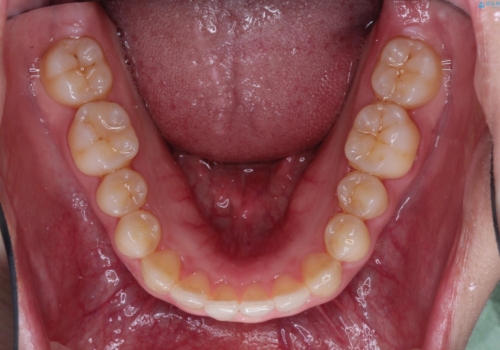

- 出っ歯の改善を希望され来院された患者様です。

初診時の歯並びの状態としては、上下とも前歯部の中等度のがたつきがあり、その他に奥歯の噛み合わせのズレや、口元の突出感も認められました。

抜歯矯正の可能性もご提案しましたが、ご本人の強い希望もあり、抜歯なし/インビザラインによるマウスピース矯正にて治療を行いました。

奥歯の嚙み合わせのズレを改善するにあたり、カリエールディスタライザーという装置を併用することで治療期間の短縮を図りました。

本症例は、見た目、嚙み合わせ及び、治療期間や施術内容にご満足いただきました。